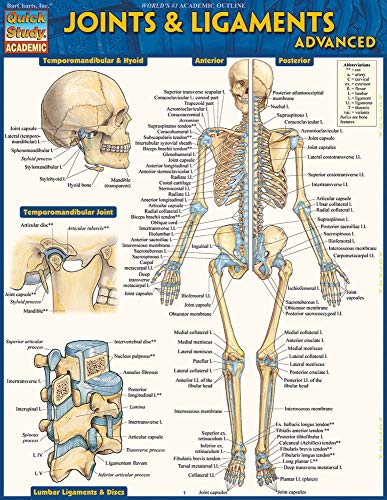

Joints & Ligaments Advanced QuickStudy Laminated Reference Guide (Quick Study Academic)